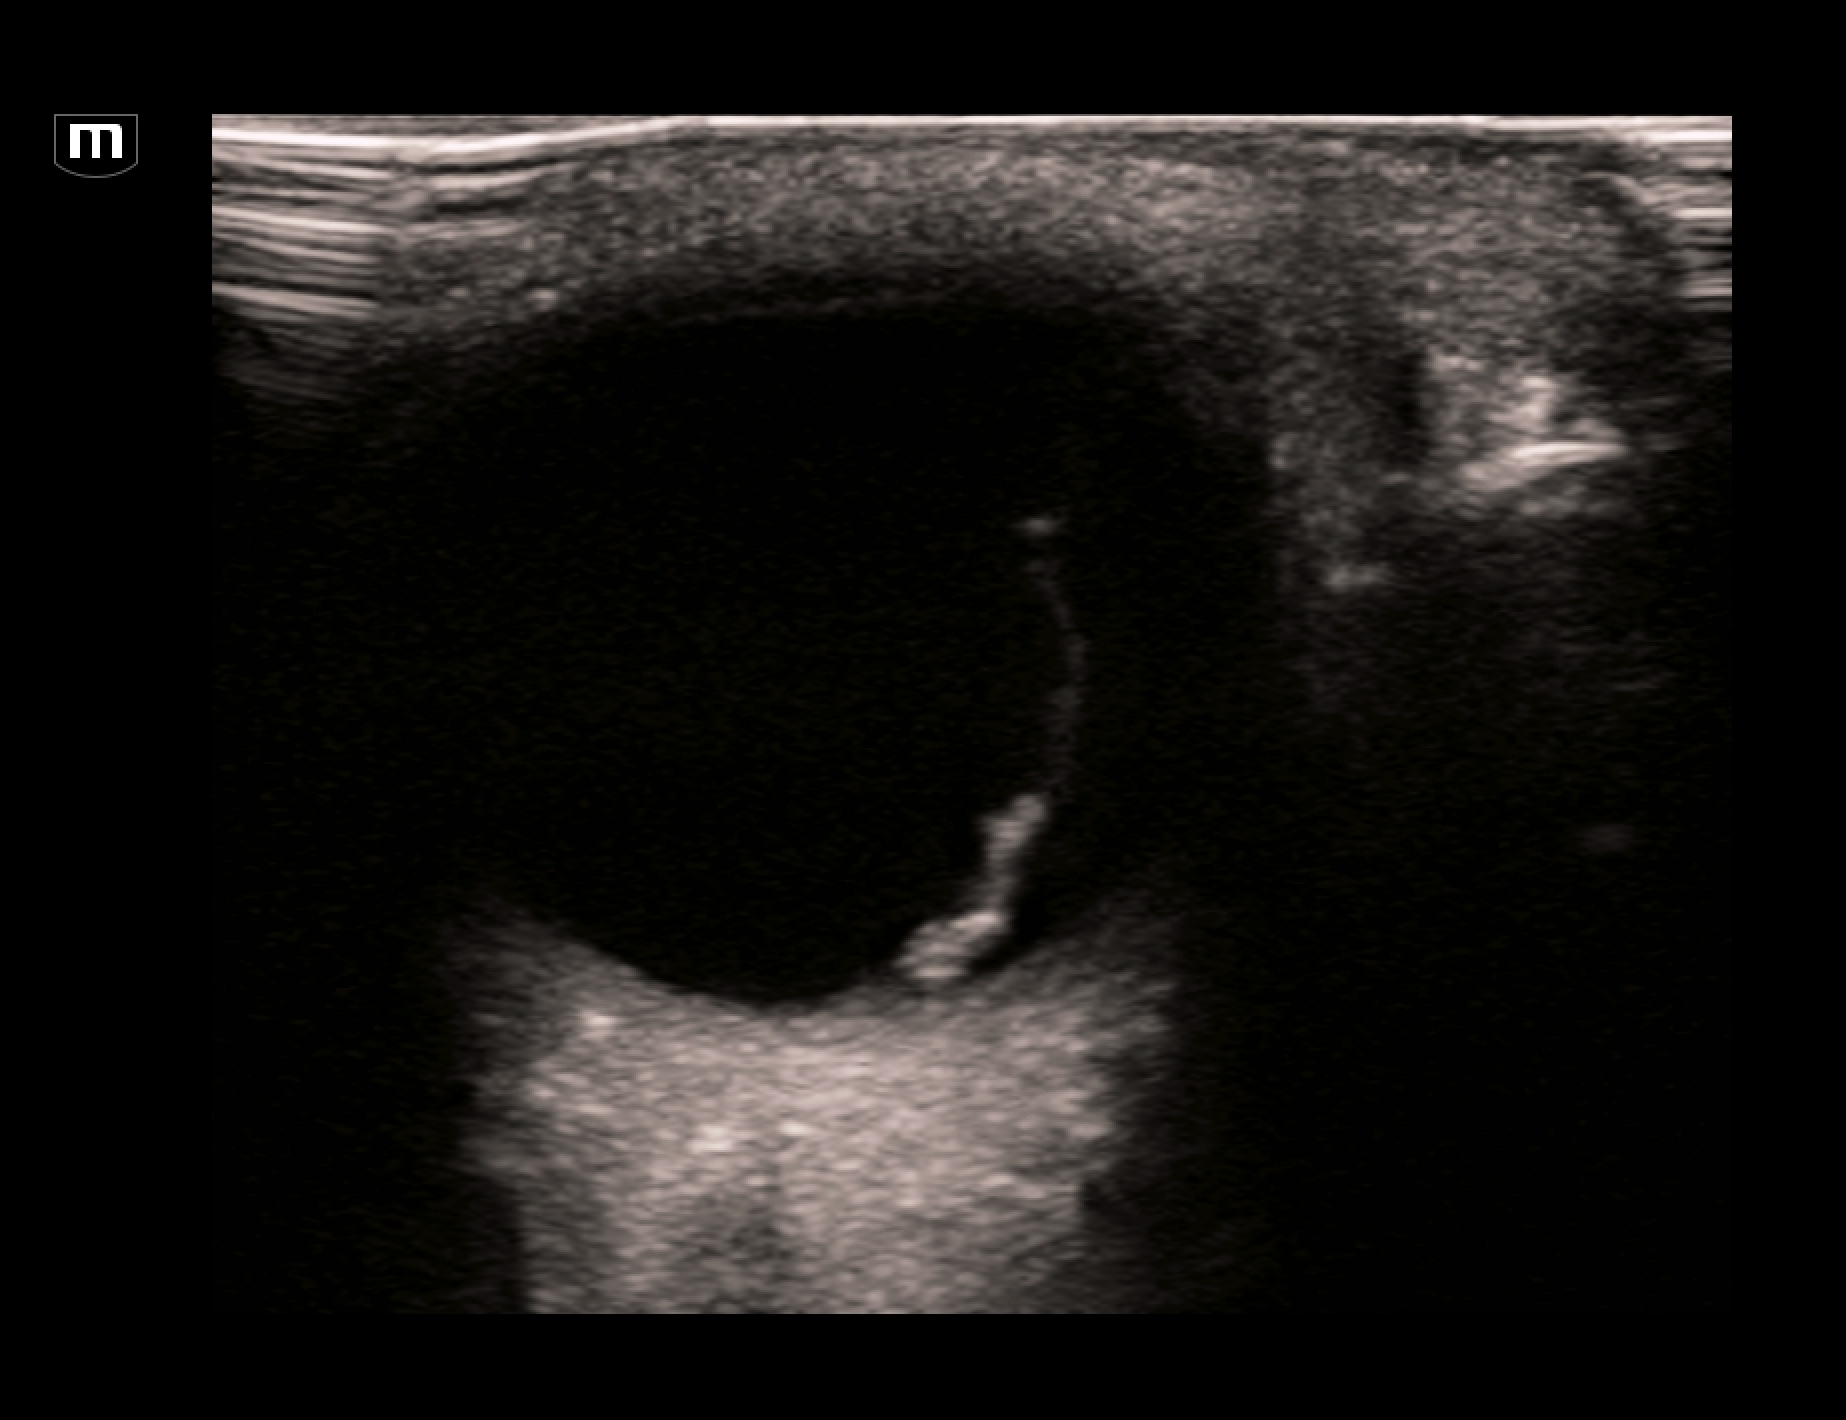

The EDUS showed this:

L orbit trans (annotated below)

This scan shows a thick hyperechoic membrane within the anechoic vitreous seeming to originate from the optic disc. This is typical of retinal detachment. Always fan through the orbit to try and image the optic nerve coming in to the orbit. A retnal detachment will be seen to be tethered to the optic disc. It does not cross over to the other side.